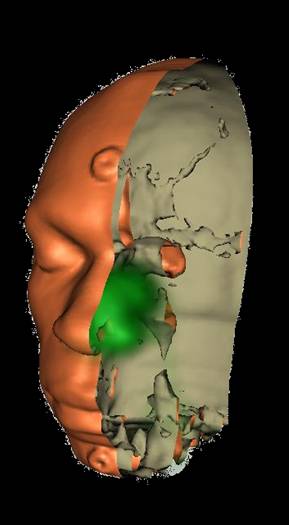

Several inhaled drug formulations were studied by radiolabeling the active ingredient (several different steriods) with C-11 or F-18, formulating that ingredient as the dosage form (different MDI, DPI, and nebulizer formulations), and performing quantitative PET studies of the regional biodistribution and kinetics.

Click on images to see additional examples, larger versions, and videos.